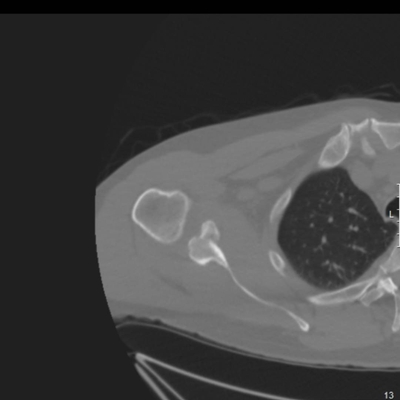

Click on an image below to view more info.